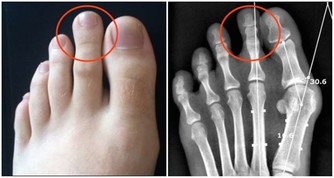

還有若你蹲下站起來後,反應特別大,明明沒有蹲太長時間,但是頭特別暈、眼花得比較厲害,需要好長時間才可以反應過來,這說明你可能有低血糖、貧血、血管問題等,血液循環不是很好,平常要注意調理下身體。